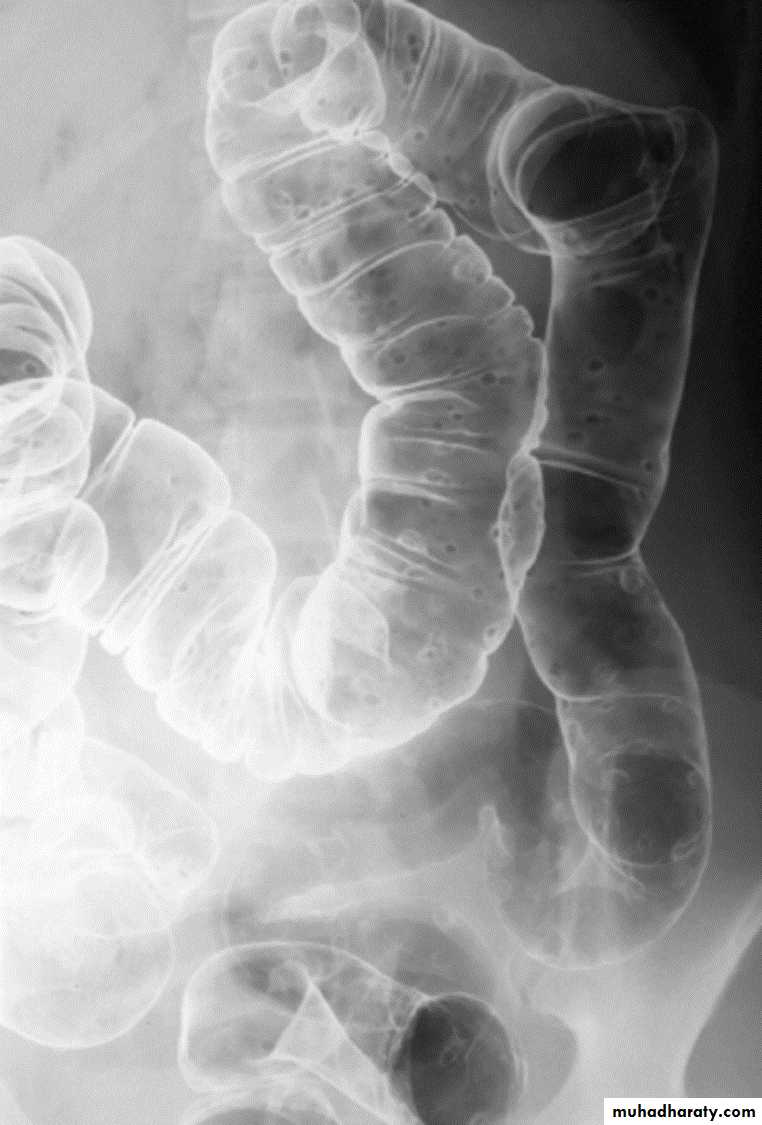

Barium enema: bowel preparation is important to get rid of the fecal material, barium is run into the colon under gravity, air is then blown in, to push the barium around the colon to give the double contrast effect. Barium enema is helpful in extensive diverticular disease being prepared for resection, colonic carcinoma, stricture, filling defect and ulceration.

Diverticular disease:

Out-pouching of the mucosa through the muscular layer of the bowel wall

Very common particularly in adults, commonest in the sigmoid.

The diverticulae when filled with barium produce a spherical out-pouching with an narrowed neck (diverticulosis), some pouches do not fill with barium when inflamed (diverticulitis) causing symptoms such as sepsis, diarrhea or obstruction.

The colon may show "saw tooth serrated" appearance from muscle hypertrophy.